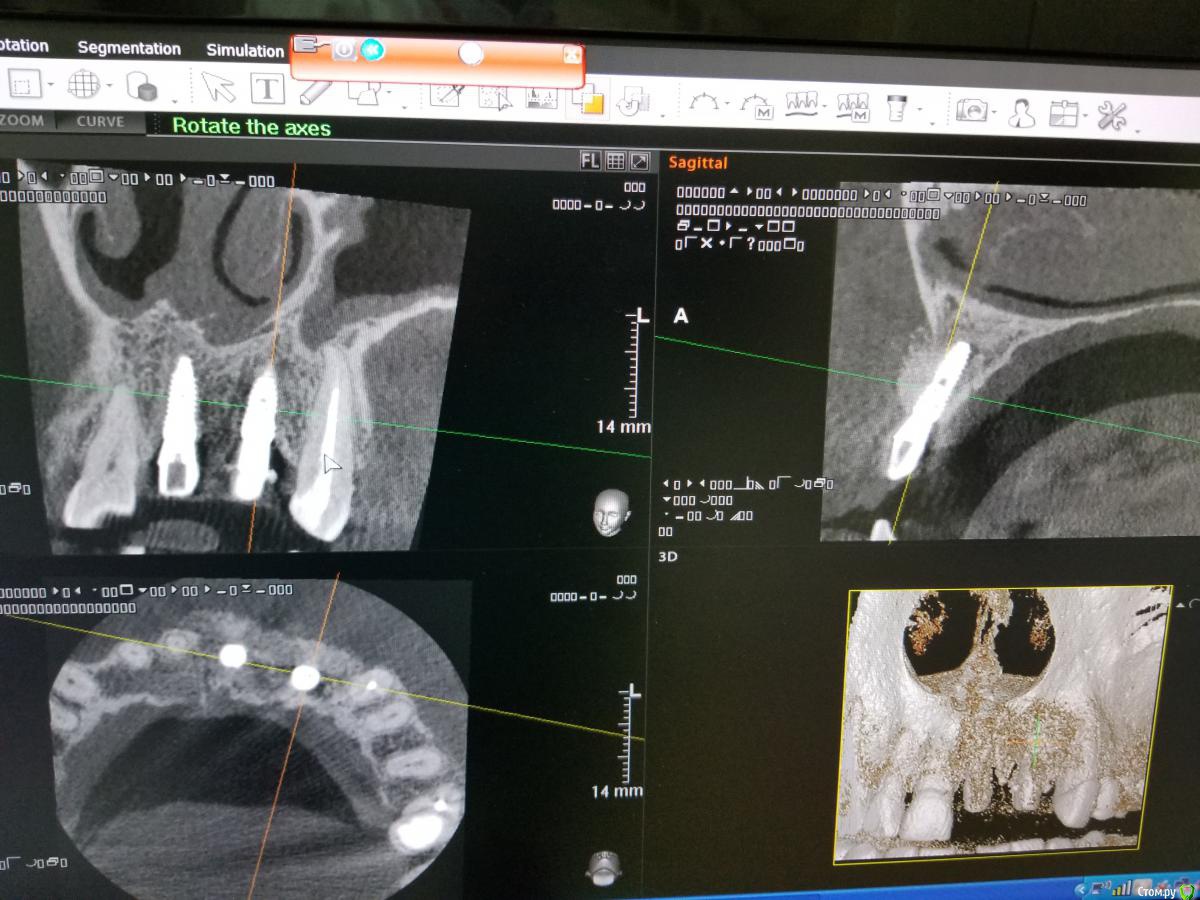

Kostoprav Опубликовано 18 сентября, 2018 Поделиться Опубликовано 18 сентября, 2018 Апатос+ ПРФ+ инъекционный ПРФ+ титановая мембрана.кт через 4,5 мес.Честно говоря кости ожидал побольше, так как паковал с гиперобобьемом. Ссылка на комментарий

stommm Опубликовано 20 сентября, 2018 Поделиться Опубликовано 20 сентября, 2018 Имхо для такого дефекта лучше сетку подлиннее (у нео есть такие) что бы апекально фиксировать в кости, а не так что апекальный край сетки лежит над дефектом. И Имплант по фото недогазлублен. Либо профиль неудачный будет, либо коронка короткая. При бОльшем заглублении имхо получилось бы лучше Ссылка на комментарий

Kostoprav Опубликовано 20 сентября, 2018 Автор Поделиться Опубликовано 20 сентября, 2018 Имхо для такого дефекта лучше сетку подлиннее (у нео есть такие) что бы апекально фиксировать в кости, а не так что апекальный край сетки лежит над дефектом. И Имплант по фото недогазлублен. Либо профиль неудачный будет, либо коронка короткая. При бОльшем заглублении имхо получилось бы лучше имплант с полированой шейкой, эго не желательно сильно погружать под кость.В инструкциях производителя этот тип мембран не предназначен для апекальной фиксации, есть мембраны с проререзями под винты но у нас таких не продают. Ссылка на комментарий

АнтонТЛТ Опубликовано 20 сентября, 2018 Поделиться Опубликовано 20 сентября, 2018 имплант с полированой шейкой, эго не желательно сильно погружать под кость.В инструкциях производителя этот тип мембран не предназначен для апекальной фиксации, есть мембраны с проререзями под винты но у нас таких не продают.Только шейка не полированная, а фрезерованная. Мембраны с прорезями это более новый вид. Мембраны без прорезей можно пробивать пином или пин/винт крепить между ножек. В вашем случае, если не прибивать, то надо было мембрану лучше загнуть или взять больший размер, чтобы мембрана опиралась на кость апикально. 2 Ссылка на комментарий